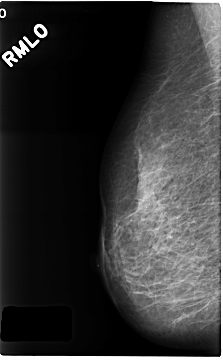

C_0216_1.RIGHT_MLO

RIGHT_CC LINES 4688 PIXELS_PER_LINE 2880 BITS_PER_PIXEL 12 RESOLUTION 50 NON_OVERLAY

RIGHT_MLO LINES 4680 PIXELS_PER_LINE 2888 BITS_PER_PIXEL 12 RESOLUTION 50 NON_OVERLAY